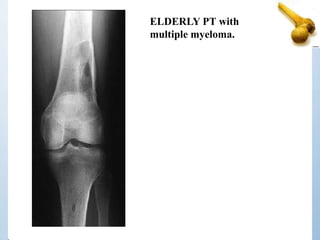

ELDERLY PT with

multiple myeloma.